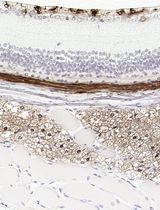

Improved Immunohistochemistry of Mouse Eye Sections Using Davidson's Fixative and Melanin Bleaching

AL Anne Nathalie Longakit

CH Chloe Hess

CZ Christina Zhang

CV Catherine D. Van Raamsdonk

1537 Views

Nov 20, 2025

Immunohistochemistry (IHC) and immunofluorescence (IF) are fundamental molecular biology techniques to assess protein expression. However, the melanin present normally in the eye in the uveal tract (choroid, iris, and ciliary body) and the retinal pigment epithelium (RPE) poses a significant challenge for IHC and IF. This is because melanin interferes with both chromogenic and fluorescent detection methods. Additionally, formalin fixation, which is commonly used for IHC, can result in shrinkage and loss of cellular detail in the eye. This protocol provides an optimized approach using Davidson’s fixative with a hydrogen peroxide bleaching step to eliminate melanin interference in the mouse eye, improving the quality and interpretability of IHC analyses of the uveal tract and RPE. It is particularly useful for the analysis of uveal melanoma.